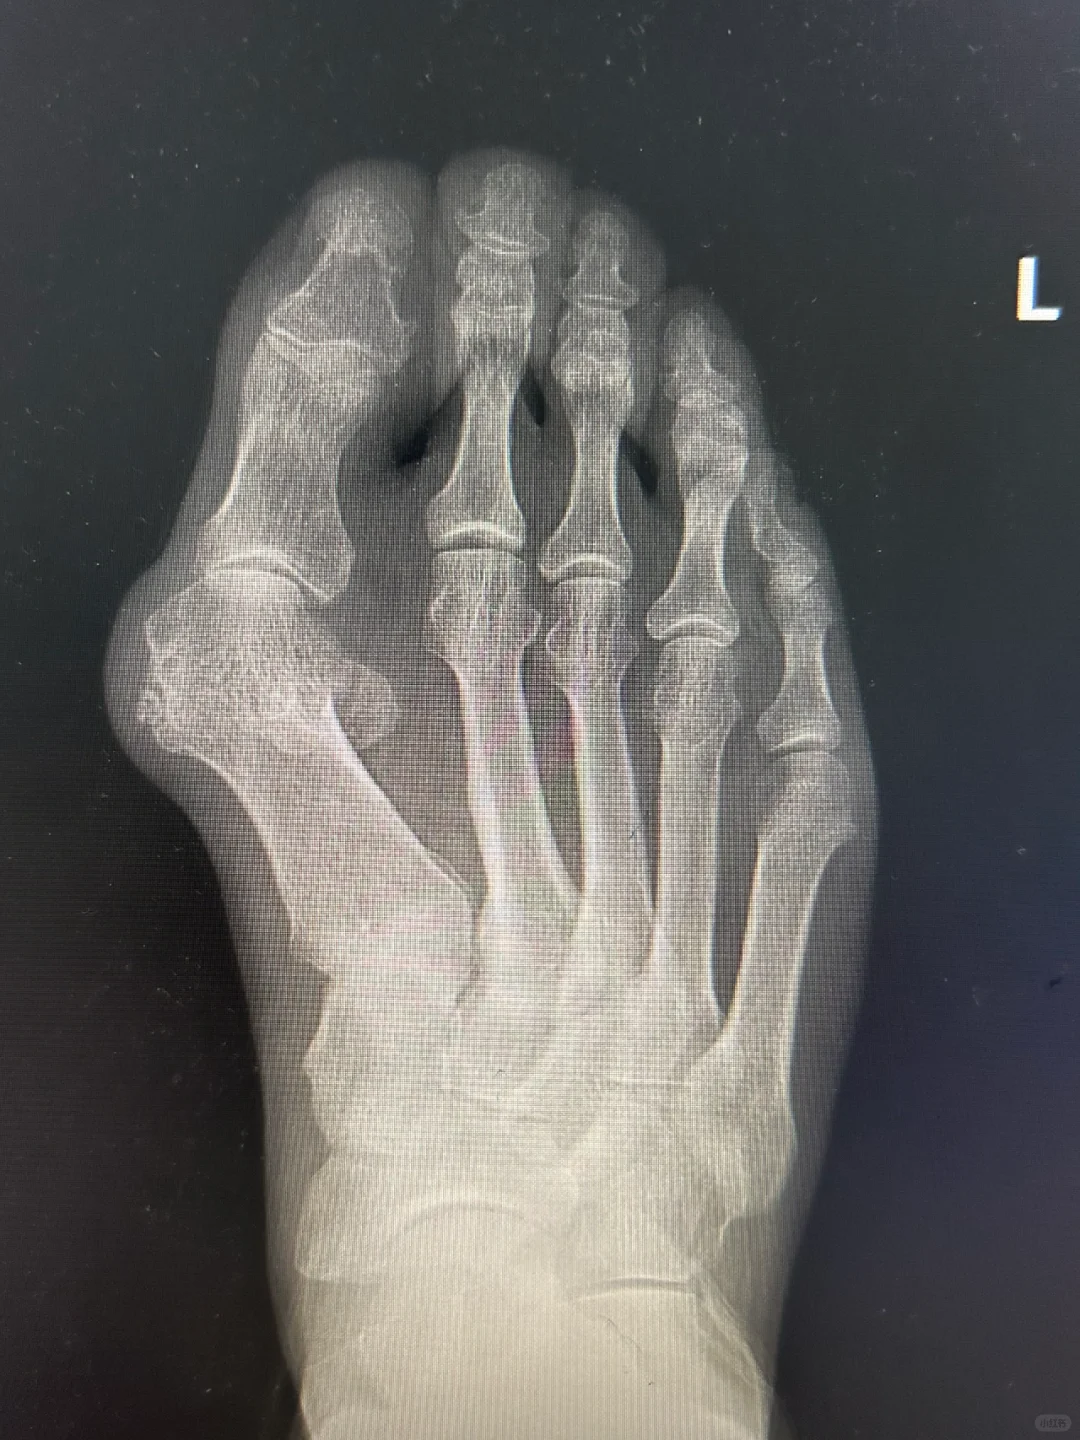

微创术后II型畸形翻修……获得研究突破